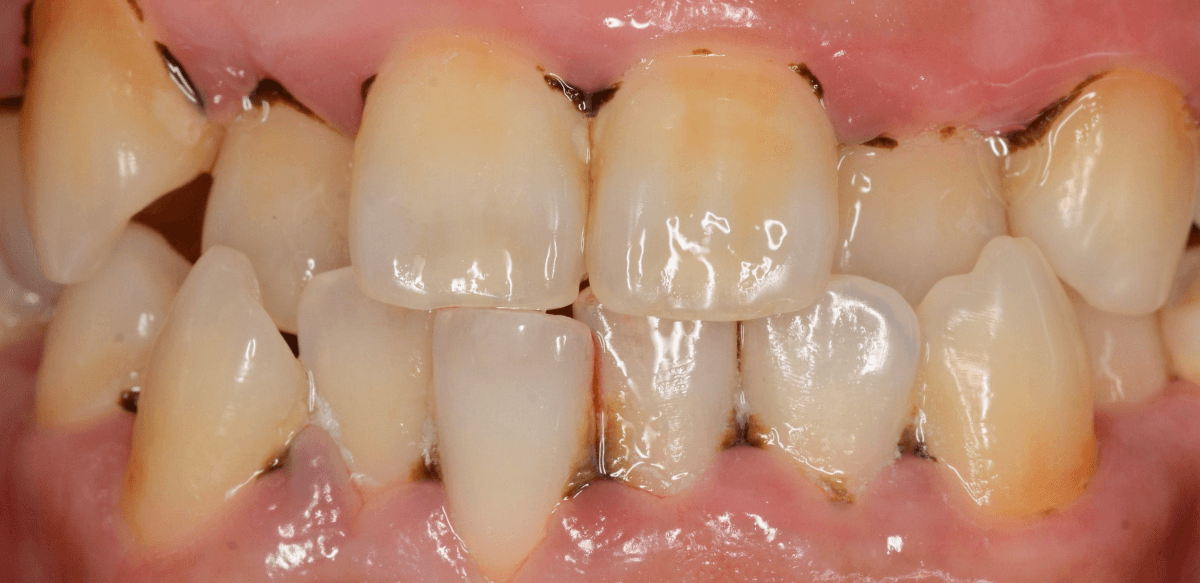

Case.4「歯の周りの黒い物を取って欲しい」という患者さん

今回は、「歯の周りの黒い物を取ってほしい」という訴えの患者さんのケースです。

着色かな、と思い口の中を拝見すると、歯の表面まで露出した縁下歯石でした。

当院は、(現在のところ)比較的若い患者さんが多いので、ここまでハッキリ縁下歯石が露出しているケースは珍しいです。

患者さんには、歯周病の基本的な説明とブラッシング指導をした後、まず下の歯の歯石除去から始めました。

ブラッシング指導・下の前歯の歯石除去直後の写真です。

これだけでも、かなり改善したかと思いますが、これだけの縁下歯石の量ですから、一回の歯石除去で全て取り切れるはずがありません。

根気よく、歯石除去を続ける必要があります。

ビフォー・アフターです。

後日、上の前歯の歯石除去を行いました。

下の前歯の歯肉も改善されてきていますね。

上の歯だけで、これだけの縁下歯石がとれました(まだ歯肉の奥には残っていると思います)。

一度では取り切れません、時間をかけて取っていく必要があります。

かなり歯肉の改善がされていますが、まだしばらく治療は続ける必要があります。